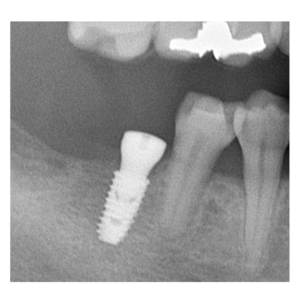

治療途中のインプラント症例

治療途中のインプラント症例です。

歯がない部分の見た目を自然にしたい |

61歳 男性 |

1時間 |

治療費(インプラント手術費) |

¥350,000(税別) |

| リスクと注意点 |

腫れ・痛み・神経損傷・インプラント周囲炎・骨吸収 など |